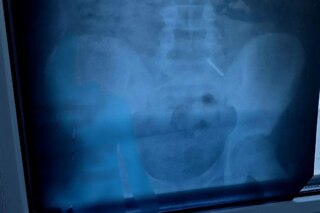

В Саратовской области подросток проглотил часть циркуля. Об этом сообщили в ГУЗ СО «Балаковская городская клиническая больница».

В публикации сказано, что случай произошёл с 11-летним ребёнком. «Почему подросток решился на столь опасный эксперимент с металлическим канцелярским товаром, установить не удалось.

Эндоскопически достать предмет не представлялось возможным из-за позднего обращения пациента. Главной задачей было не допустить перфорации кишечника и кровотечения — мальчик находился под наблюдением врачей и рентгенологов. В итоге инородное тело вышло естественным путём. Пациент выписан домой», — рассказали врачи.